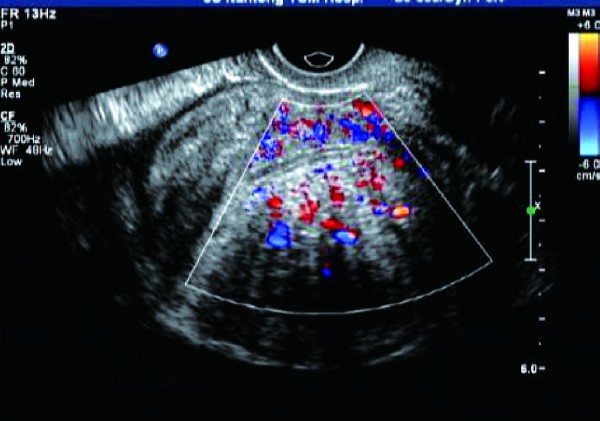

即子宫腺肌瘤,呈边界不清的团块状回声,呈不均质高回声,病灶与正常肌层间没有清晰的边界,即无包膜回声;彩色血流信号丰富,病灶周围无环状彩色血流信号。

子宫肌瘤:①子宫肌瘤可见假性包膜,边界清晰;子宫腺肌症无包膜,与周围组织界限不清。②子宫肌瘤以低回声较为多见,多成旋涡样改变;子宫腺肌症多以弱强回声多见,无明显旋涡状结构。③子宫肌瘤周边血供多于内部,周围有环状血流信号;子宫腺肌症周围无环状彩色血流信号。

经阴道彩色多普勒超声能清晰显示子宫肌层病变的大小、部位、范围,而且能清晰显示其内部结构变化。超声检查时重点观察子宫肌层病灶回声、病灶周边无包膜及病灶内小片状血流信号等特征性表现,能提高诊断符合率。